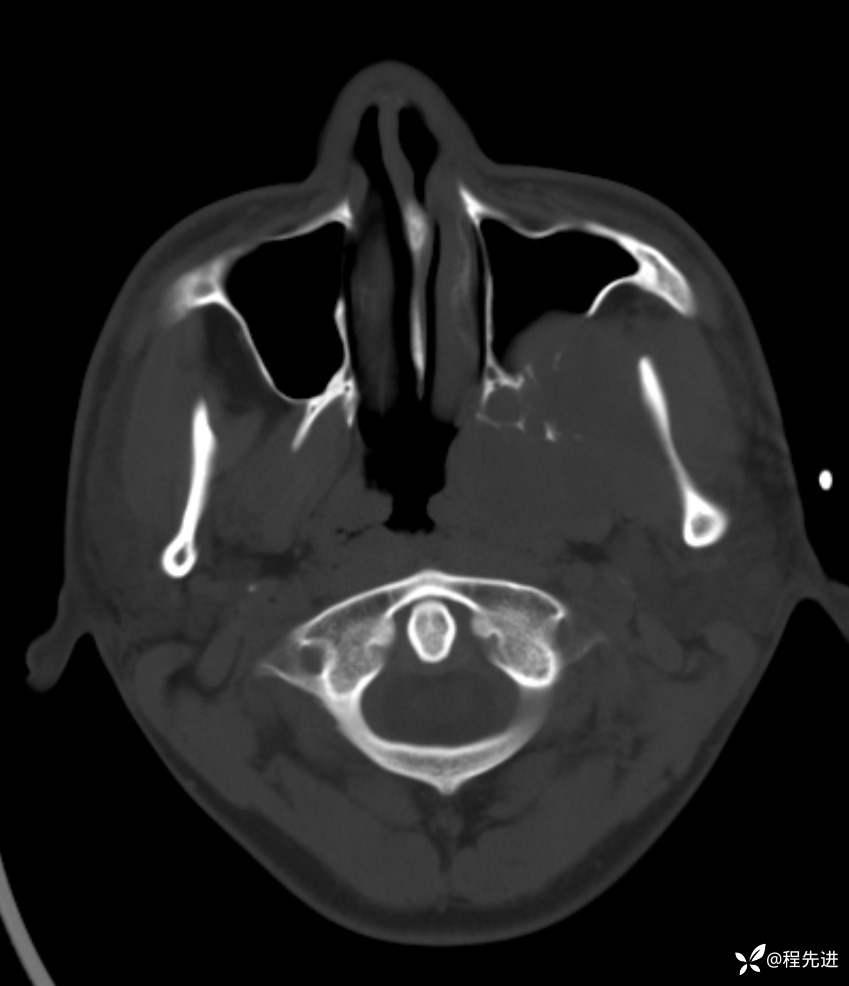

简要病史:左眼视力下降20余天,伴肿胀疼痛不适半月

骨窗:

薄层完整视频: